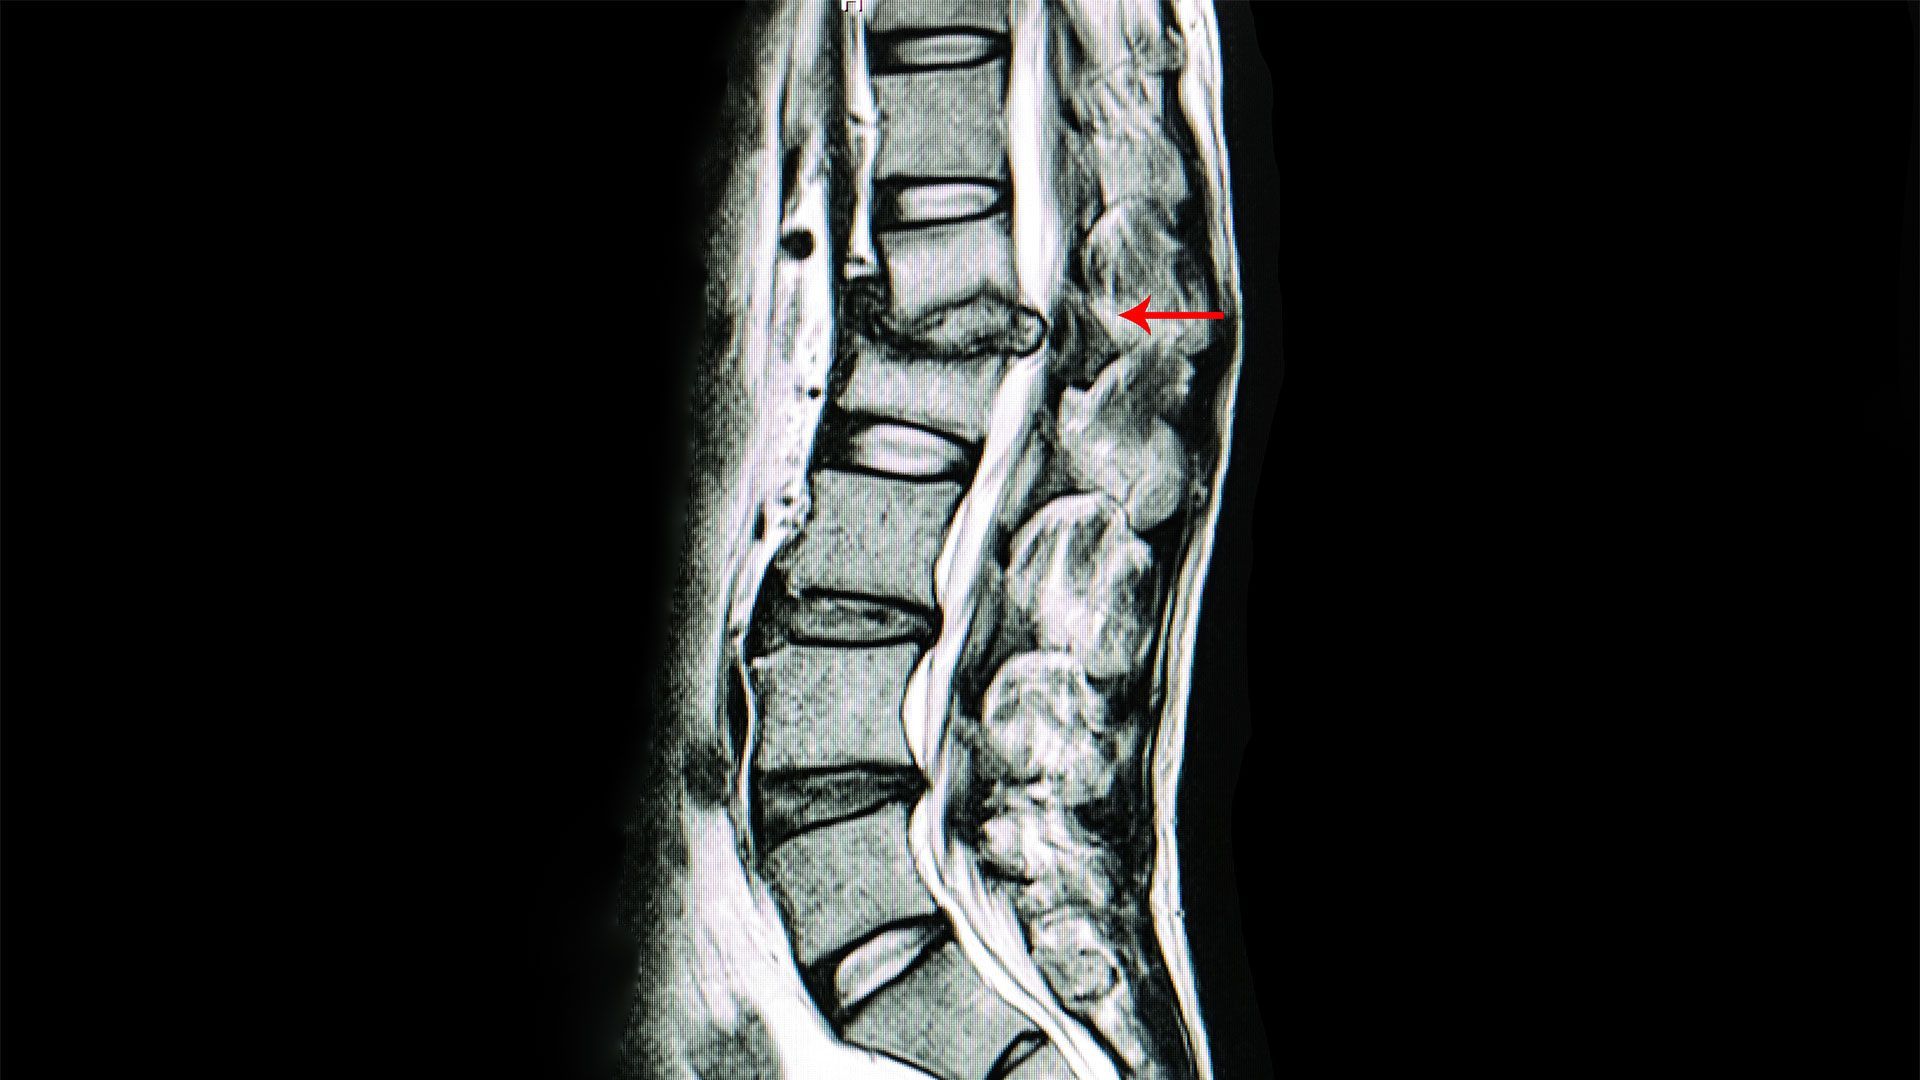

Spine MRI

By Dukes Chiropractic March 5, 2026

MRI findings don’t always explain your pain. Discover how conservative chiropractic care in Plant City helps restore function without surgery or opioids.